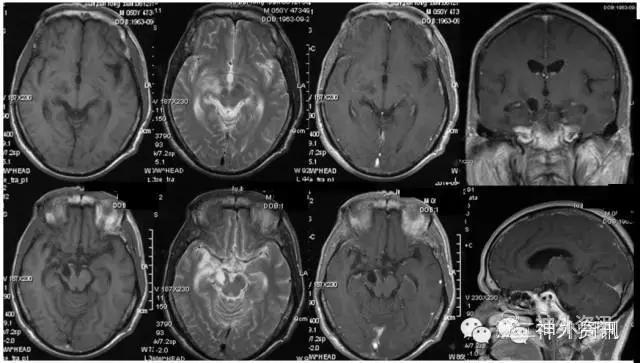

患者:男,50岁,因“左侧肢体乏力伴疼痛进行性加重1月”,经门诊MRI等检查(图1),诊断为“右侧脑干胶质瘤”收入院。

图1. 术前头颅MRI示:右侧中脑病变,上方累及丘脑底部,下方累及桥脑,病变沿神经纤维束走行,T1WI呈低信号,T2WI呈高信号,增强扫描未见病灶内强化,考虑低级别星形细胞瘤。